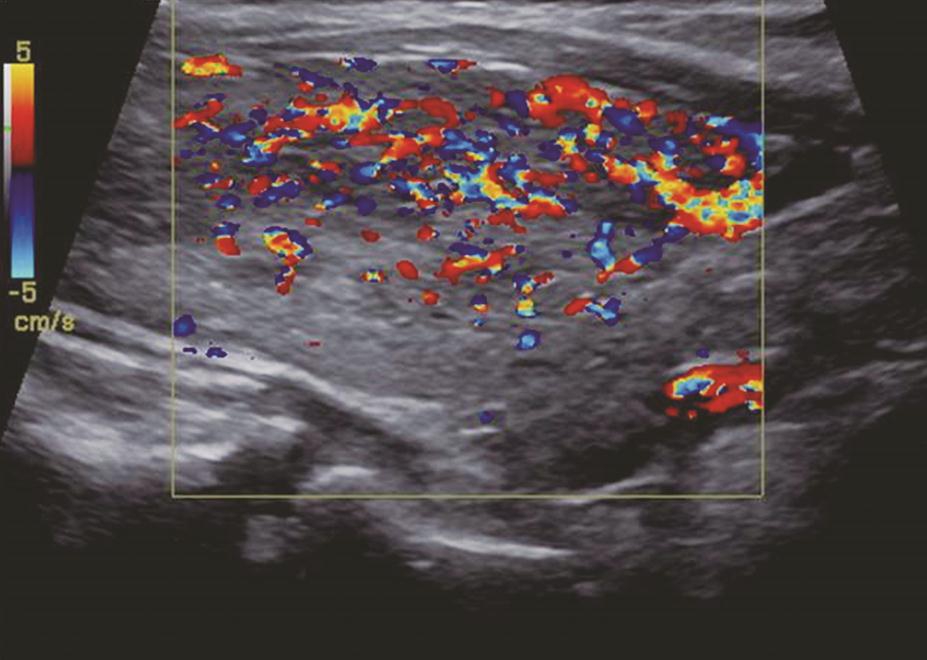

甲状腺滤泡癌和滤泡腺瘤在超声上鉴别有一定困难,即使是FNA细胞学也很难鉴别。但有报道认为:与甲状腺乳头状癌不同,甲状腺滤泡癌常为等回声或高回声,微小钙化很少见,病变多伴有厚薄不一的低回声晕或者局部低回声晕。彩色多普勒血流信号丰富也是该类病变的特点之一(图11、图12)。

:中等回声彩色多普勒血流信号丰富而杂乱.jpg)

图12右侧颈部纵切面(与图3-3-11同患者、同切面):中等回声彩色多普勒血流信号丰富而杂乱